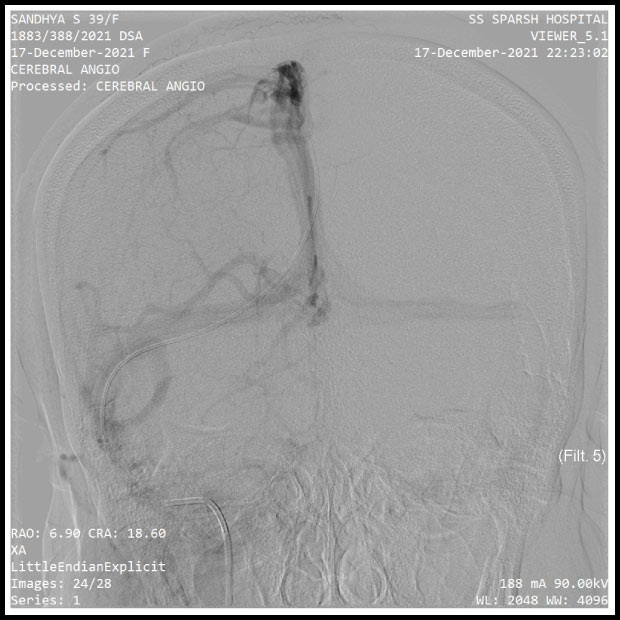

TEST REPORTS FROM THE HOSPITAL

Pics show the test reports from the hospital. The brain aneurysm is clearly noticeable.